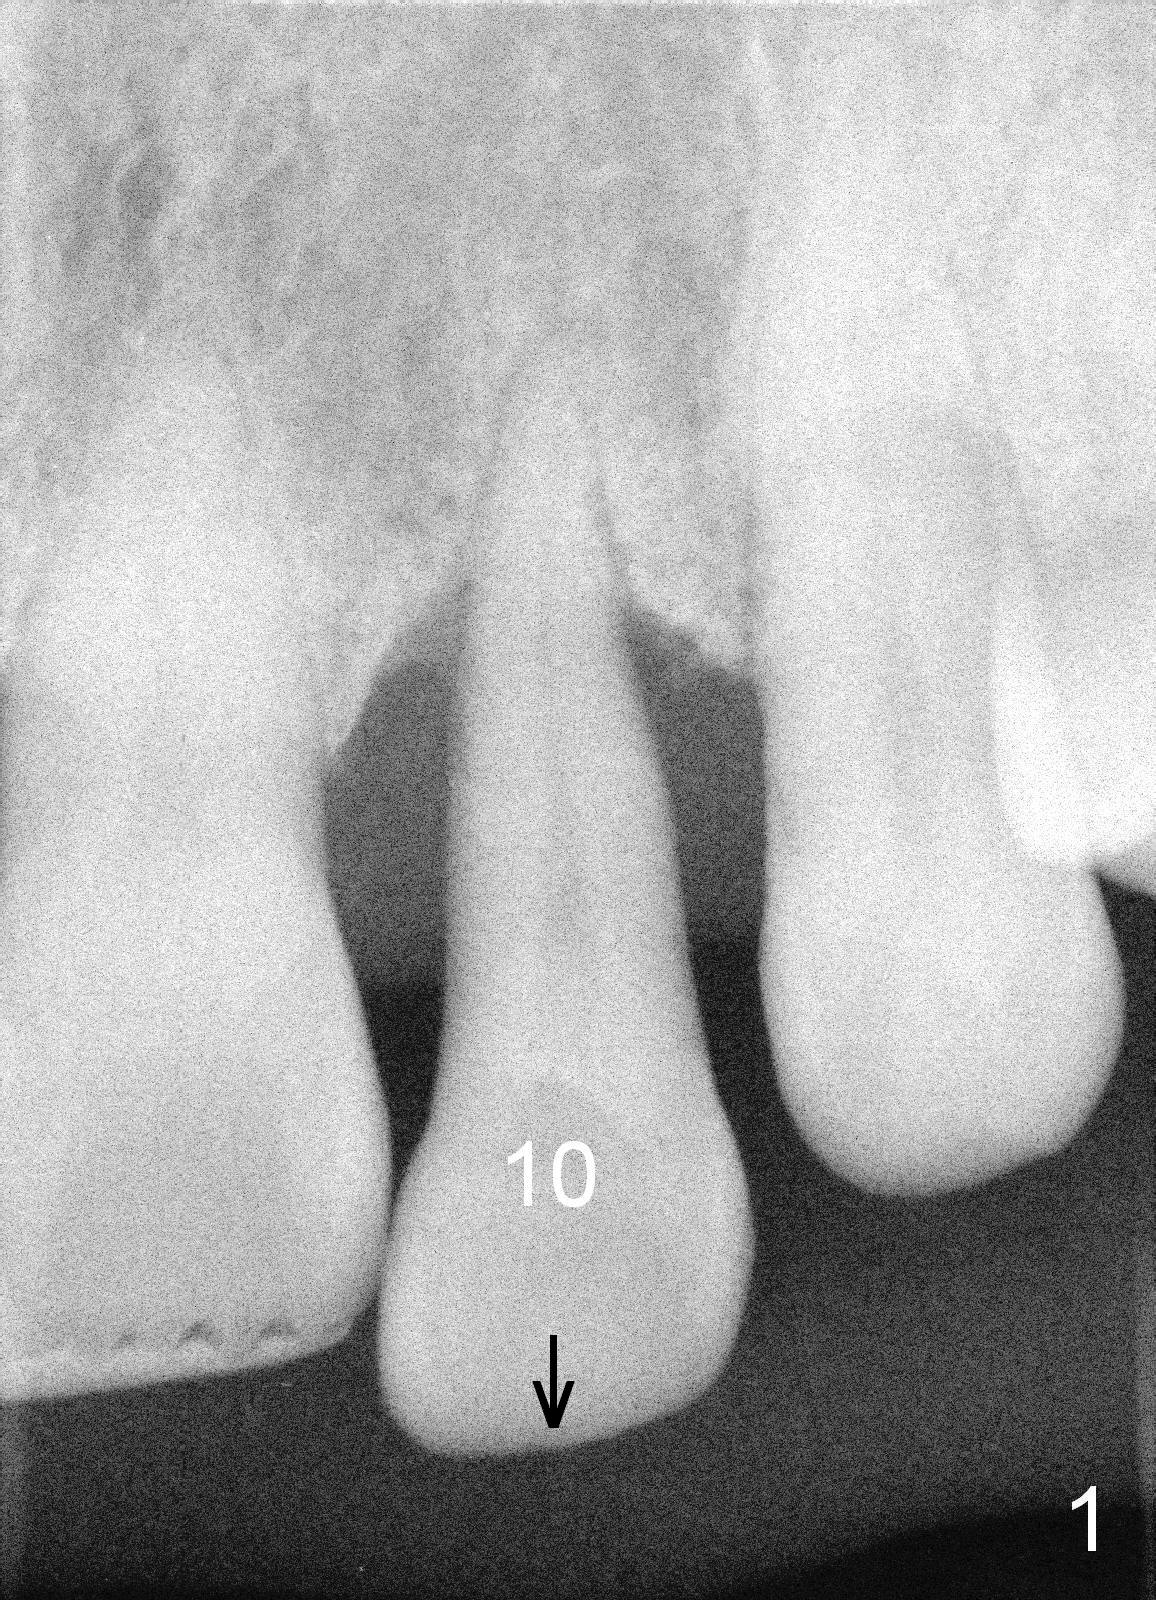

A 46-year-old lady has severe chronic periodontitis. The tooth #10 has drifted inferiorly and labially (Fig.1). One month and a half after #31 immediate implant, she wants to take care of #10. After extraction, measure the socket and tooth dimension. The implant (green box in Fig.2) diameter should be at least 2 mm smaller than the buccopalatal width of the socket. The platform of the implant should be 2-3 mm superior to the CEJ (cementoenamel junction (arrowheads)) of the neighboring teeth. The exposed implant threads will be covered by bone graft (red circles). Since the gingiva is thick (coronoapically), the abutment (gold color) cuff is expected to be 3-4 mm.